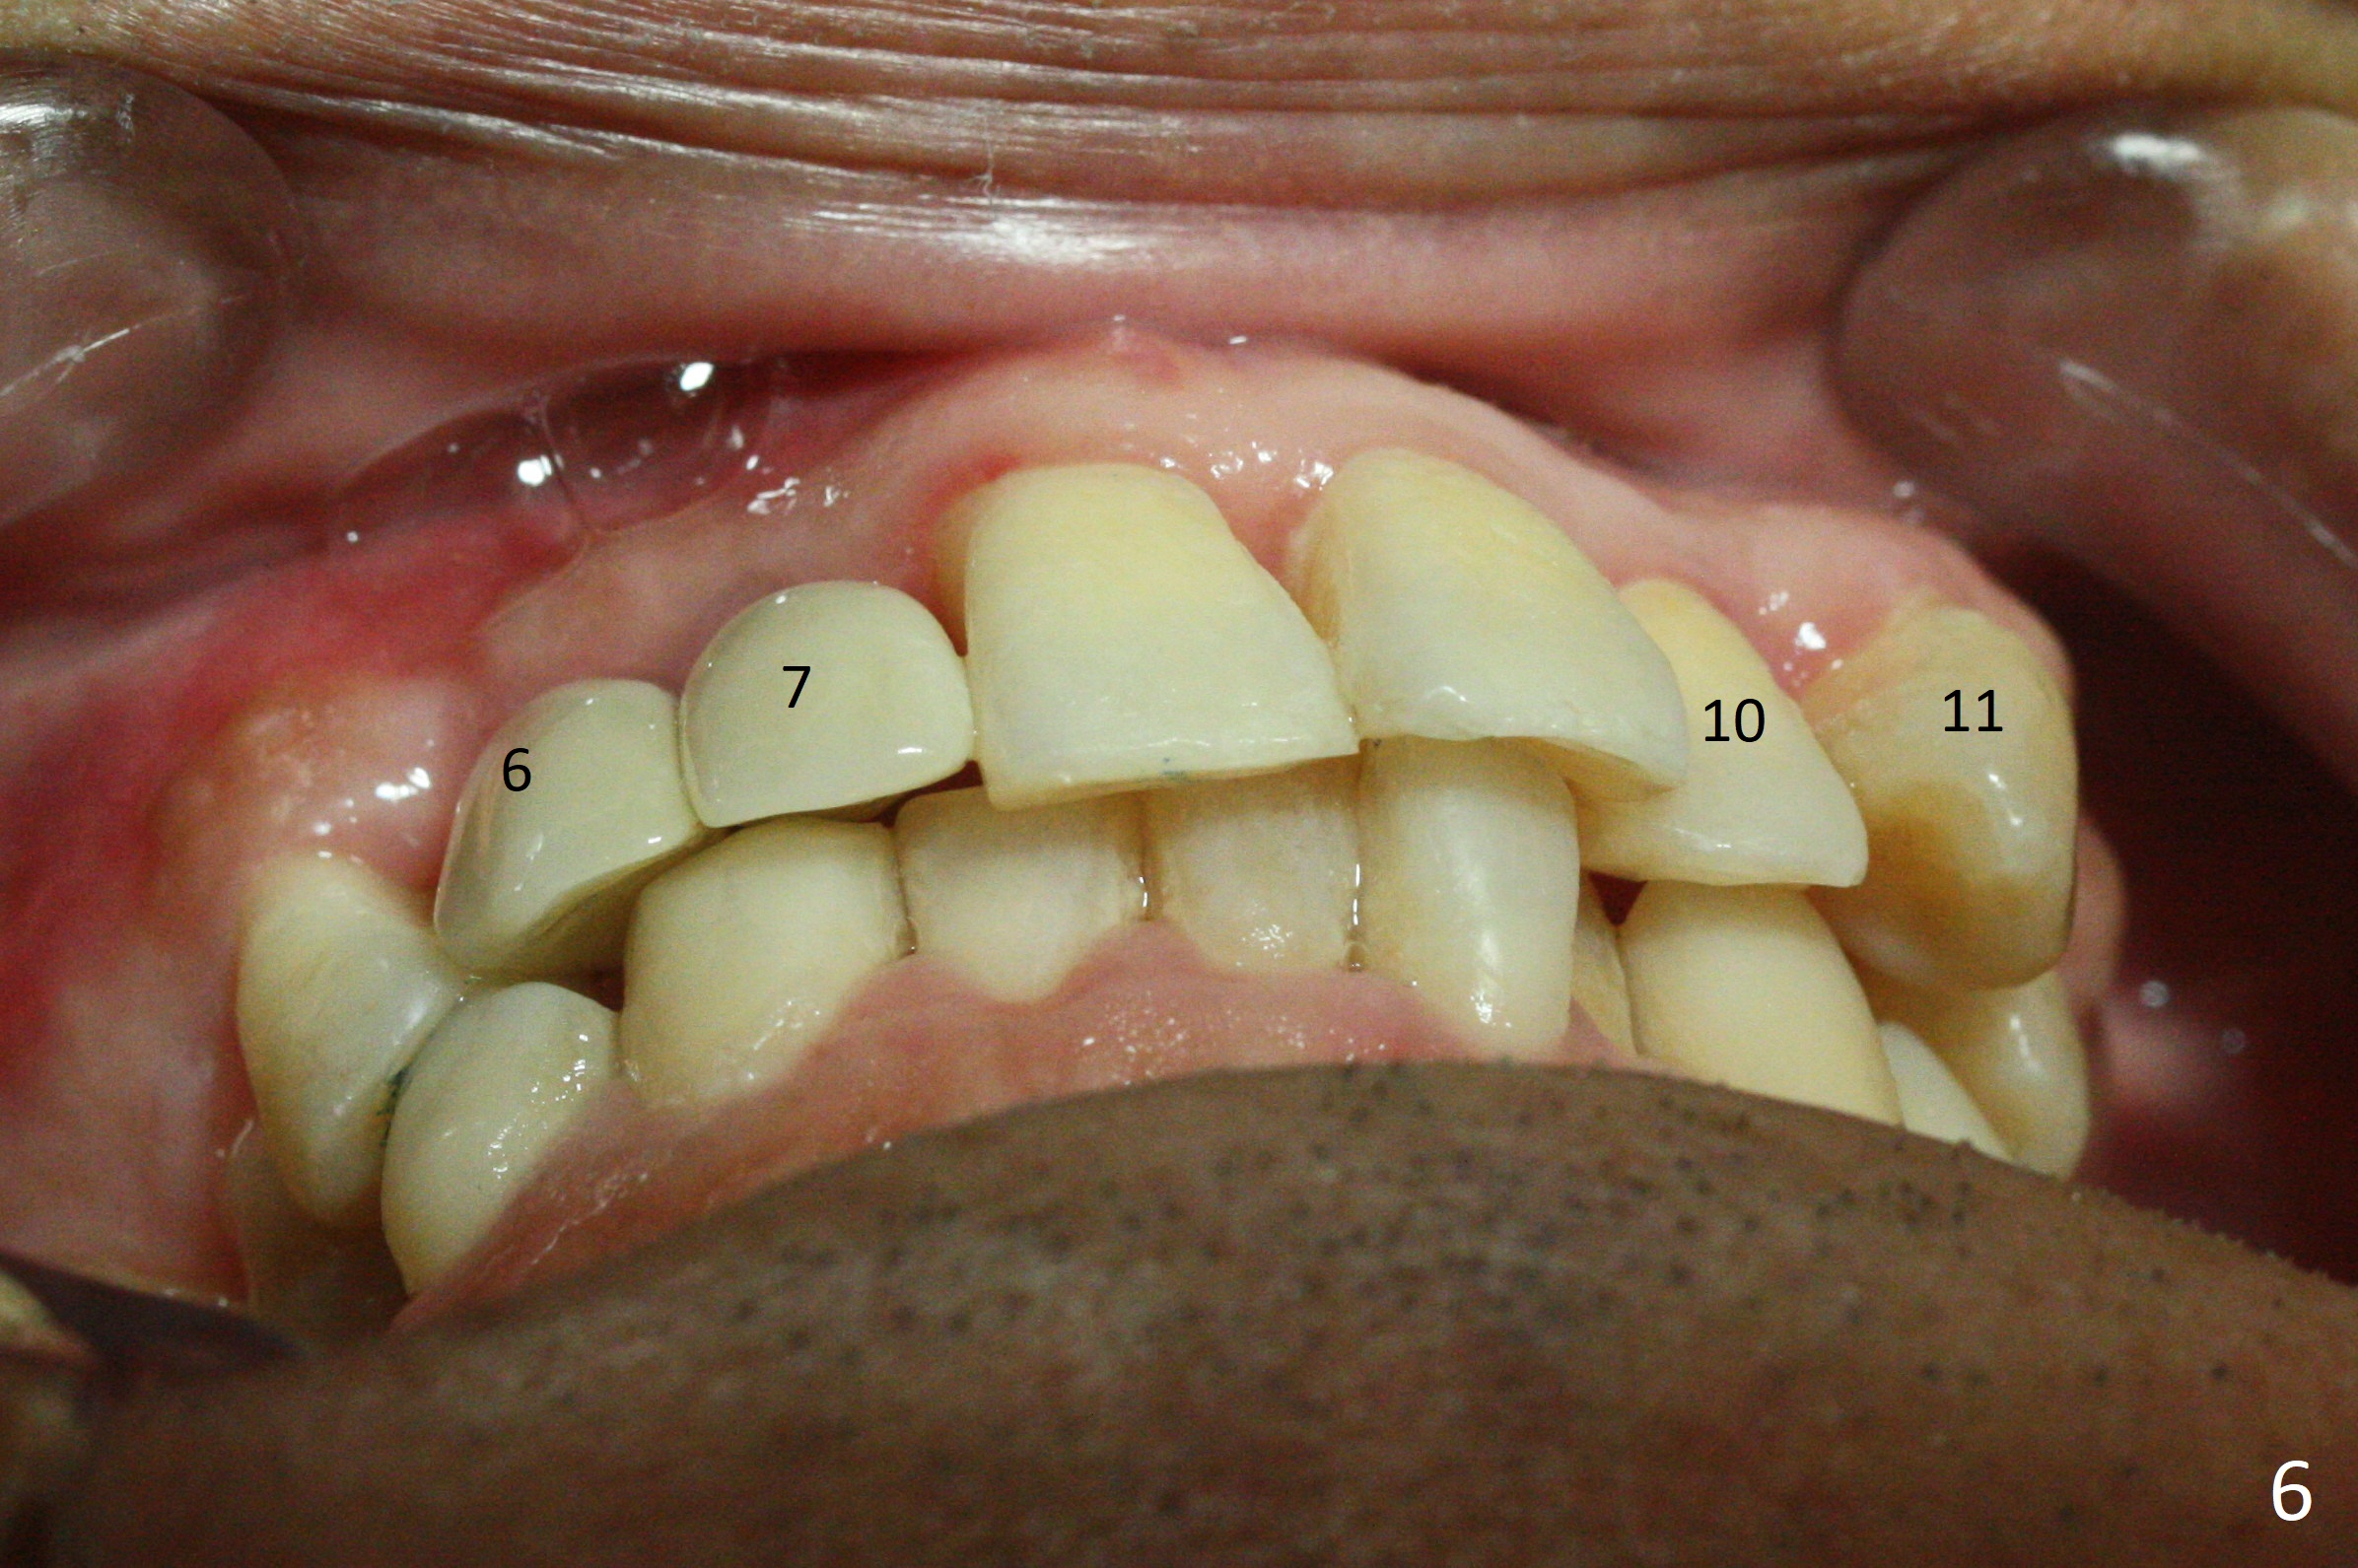

There is no bone loss 3 months postop (Fig.3). After reprep (Fig.4), shades are selected for the final crowns (Fig.5). Before crown cementation at #6 and 7, the patient notes asymmetry with the teeth on the other side (Fig.6). Our concerns are the lack of the papilla distal to #6 (Fig.7 * (multiple modification of provisional needed)) and slight inflammation due to insufficient oral hygiene (^).